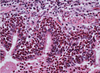

Tissue from a raven; what is the etiology?

Poxvirus